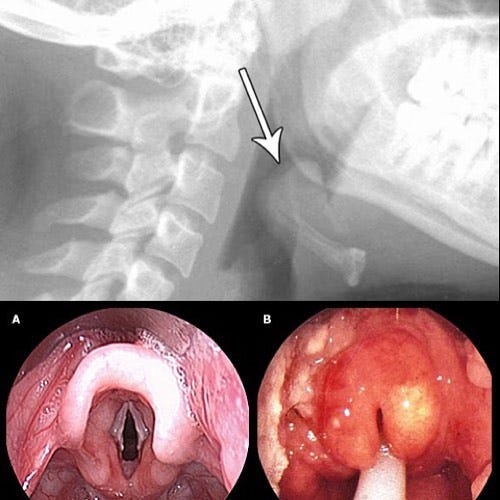

In fact, the average pediatrician under age 60 has likely never treated a child with epiglottitis!

And believe me, no one wants Hib infections to return!